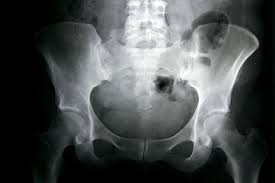

In skeletal traction, a pin (eg, a Steinmann pin) is placed through a bone distal to the fracture. Weights are applied to this pin, and the patient is placed in an apparatus to facilitate traction and nursing care. Skeletal traction is most commonly used in femur fractures: A pin is placed in the distal femur (see the image below) or proximal tibia 1-2 cm posterior to the tibial tuberosity. Once the pin is placed, a Thomas splint is used to achieve balanced suspension.